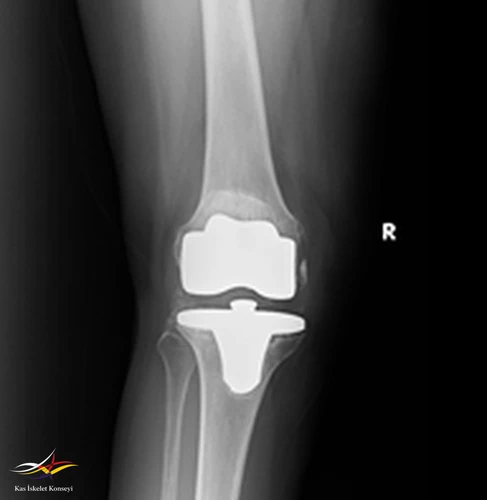

Hikaye: Dört yıl önce sağ dize total protezi uygulanan hastanın üç ay önce ortopedi kliniğine aynı dizde ağrı ve eklemde kısıtlılık ile başvurduğu ve mevcut protezin revize edilmesi kararı verildiği öğrenildi. Başvurmasından iki ay önce revizyon diz protezi yapılıyor. Ameliyattan sonra düşük ayak gelişiyor. Ev egzersizleri, ortez ve multivitamin ile taburcu ediliyor.

Muayene: Sağ ayak dorsifleksiyon kas gücü 0/5, diğer kas güçleri tam. Sağ diz EHA fleksiyon aktif 100 dereceye kadar ağrısız, ekstansiyon tam. Pasif EHA 110 derece ağrısız.